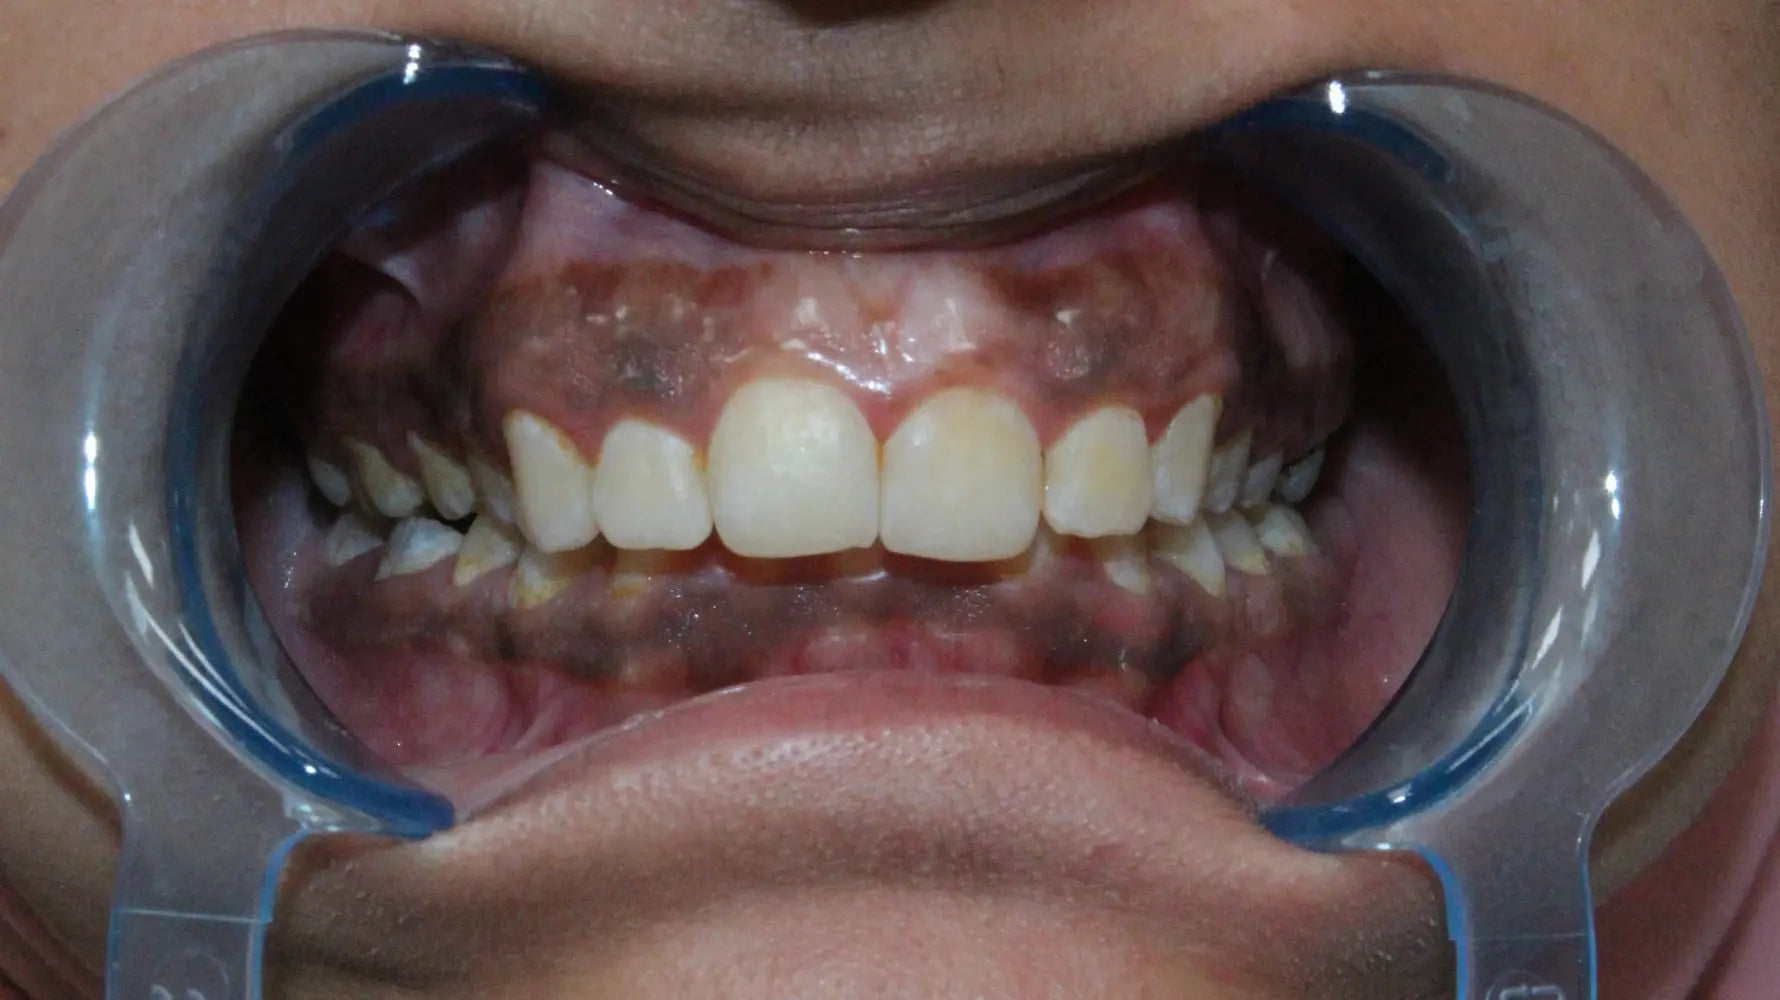

Let's start with the basics. Gum hyperpigmentation - also called gingival hyperpigmentation - is the medical term for darkening of the gum tissues. Think of it as the oral equivalent of having freckles or age spots on your skin.

This darkening typically occurs when there's an increased deposit of melanin (the same pigment that gives your skin and hair their color) in the gum tissue. Sometimes it's caused by changes in blood vessels, medications, or underlying medical conditions.

For many people, darker gums are simply part of their natural coloring. This is especially common among individuals with darker skin tones. According to research published in the Journal of Periodontology, melanin pigmentation in gingival tissue is a normal physiological variation and appears more frequently in certain ethnic populations.

Think of it this way: just as people have different skin tones, they also have varying levels of melanin in their gum tissue. There's nothing abnormal about this - it's simply genetic diversity at work.